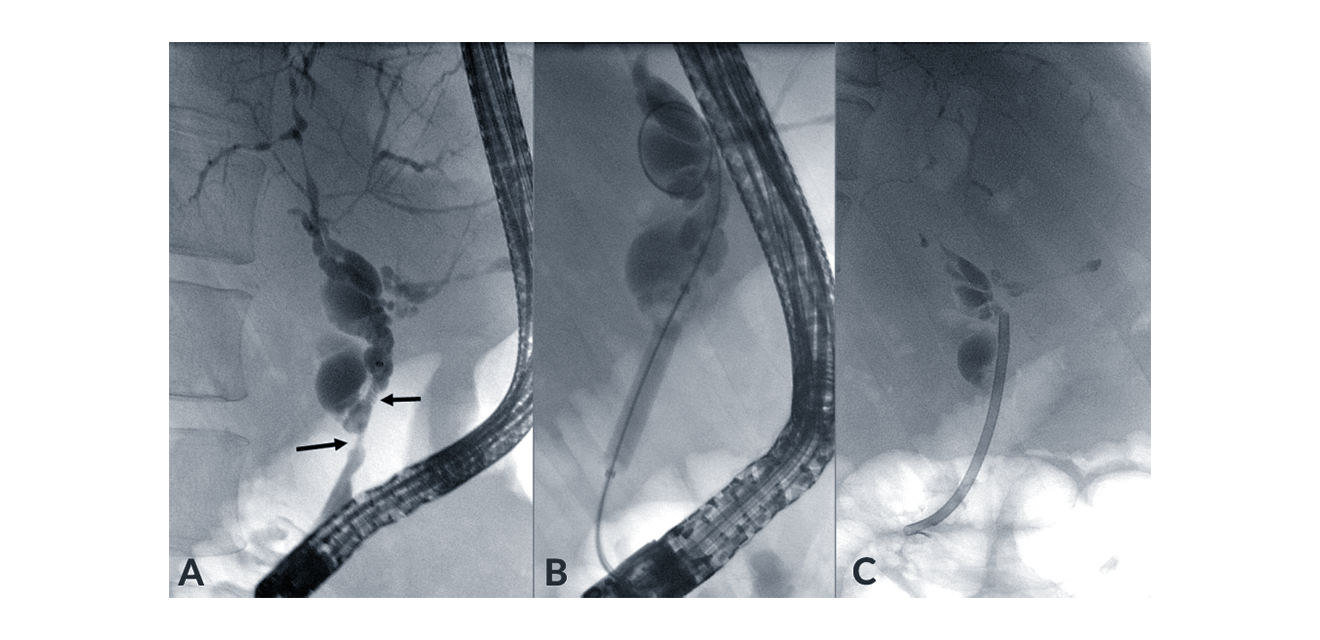

Fibrotic strictures of the bile ducts with consecutive bile duct dilatations characterise PSC, promote ascending cholangitis, and lead to cholestasis. Mechanical balloon dilatation (Figure 5) of these strictures using ERC can effectively resolve cholestasis and relieve symptoms of cholestasis (Gluck 2008, Gotthardt 2010). According to a recently published international randomised trial (Ponsioen 2018), short-term stent insertion is not less effective than ballon dilatation but was associated with significantly more complications. Therefore, balloon dilatation should be the preferred method, and stent implantation of PSC-associated bile duct strictures should be used cautiously only in selected cases. Choledocholithiasis, which is occasionally associated with PSC, can also be treated endoscopically by means of balloon or basket assisted stone removal or mechanical or electrohydraulic lithotripsy.

Figure 5. Endoscopic treatment of a high-grade stricture (A) with either balloon dilatation (B) or stenting (C). Combination of both methods is also frequently applied.